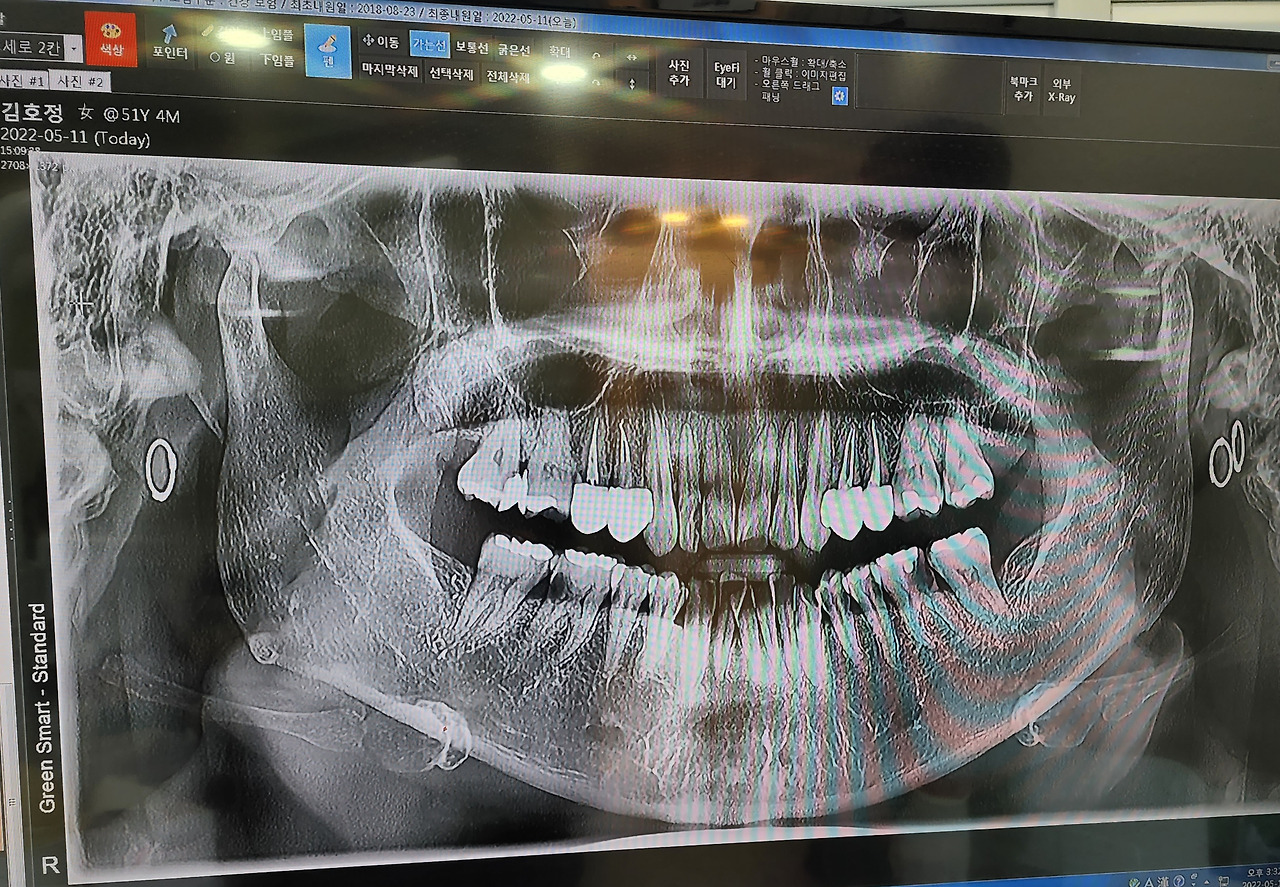

통증을 일으키는 여러 가지 병들이 잠깐의 쉴 수 있는 시간도 주지 않은 채 고통 속에 몰아넣는 바람에 어금니의 잇몸이 녹아내리고 어금니 앞니와 위쪽 송곳니 뒤쪽에 깨진 이가 3나 되었다.

거기에 더불어 위쪽의 앞니 네다섯 대를 제외한 모든 이가 썩어 충치가 되어 있었다. 이가 아프긴 했지만 이런 식으로, 이렇게 많이, 이렇게 갑자기 치과 치료가 급한 불똥이 되어 떨어질 것이라 생각해 본 적 없었다.

아래쪽 다섯 개와 위쪽 앞니 2개가 다 심하게 썩어 있었다. 여러 가지 일들(가정사, 딸의 치료 방법 변화, 제 신경과 주치의 교수님이 병원 옮기신 일, 친정과의 문제... 기타 등등)로 인해 양쪽 이와 턱이 너무 아픈데도 불구하고 두 달이나 시간을 끌다 치과를 방문했고 이제야 막 치료를 시작했다.